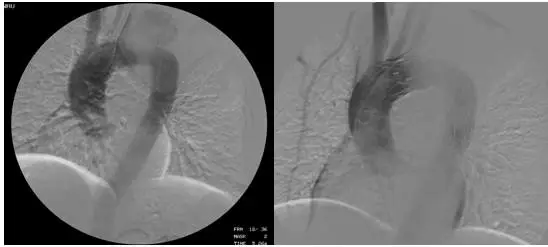

主动脉夹层介入治疗

在肖纯副院长指导下,由钟思干主任、廖火城和刘建平医生为核心的大血管团队经过详细的论证,最终决定为该患者实施支架植入的介入治疗。历时70余分钟,以廖火城医生为核心的大血管团队以精湛的技术为患者实施了胸主动脉腔内覆膜支架植入术,主动脉瘤合并夹层同时成功隔绝,且无大动脉内外瘘、截瘫、脑梗塞、消化道出血等并发症发生,患者体内“定时炸弹”被成功拆除!